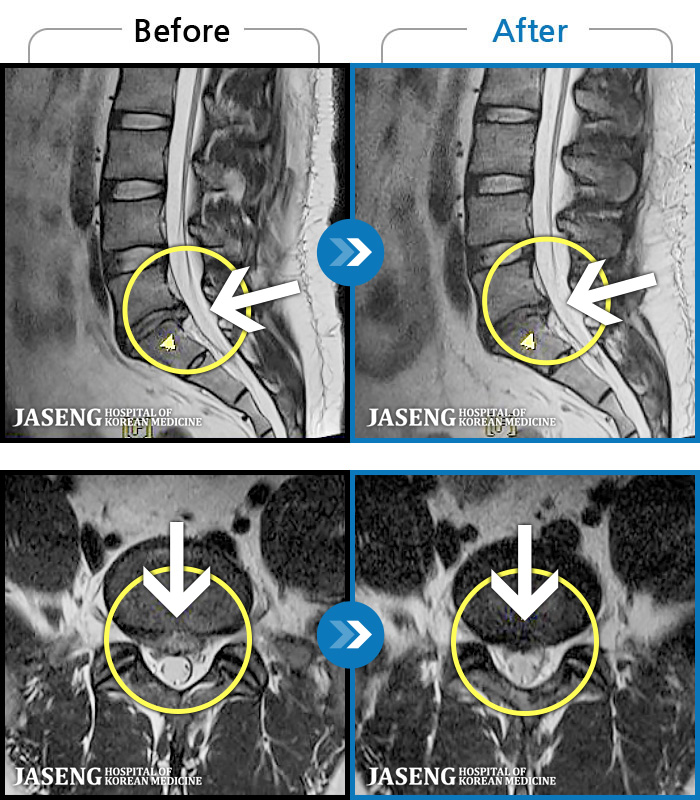

Before

After

환자에게 사전 동의를 받아 동일 조건에서 촬영되었습니다.

개인에 따라 치료 후 부작용이 발생할 수 있으니 의료진과 상담 후 치료를 진행하시기 바랍니다.

허리, 좌측 골반부터 좌측 다리로 통증 및 저림이 지속되고 좌측 다리의 감각이 둔함

증상이 재발하였습니다.